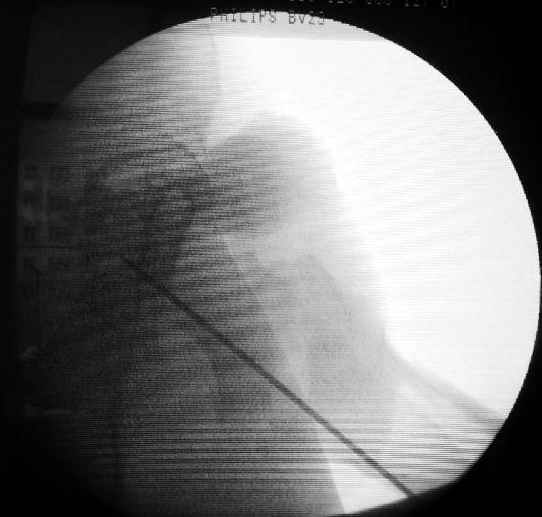

Второй случай тоже репозиция из малого доступа, больному 19 лет, множественные огнестрельные повреждениия конечностей, живота и черепа, правая конечность холодная, без пульсации. Ортопедический диагноз: огнестрельный перелом правого бедра. При срочной ангиографии повреждения сосудов не подтвердилось, конечность из-за ургентности состояния больного зафиксирована временным наружным фиксатором и больной оставлен на операционном столе для срочной лапаротомии хирургической службой.

Больной долго оставался нестабильным, только на 14 день удалось заменить на антеградный интромедуллярный штифт TFN (trochanteric femoral nail) SmithNephew. После неудачной попытки закрытой репозиции, несмотря на использование "joystick", проксимальный стержень от

наружного фиксатора, (перелом начал срастаться) репозицию провели из малого доступа, затем остальные этапы операции.